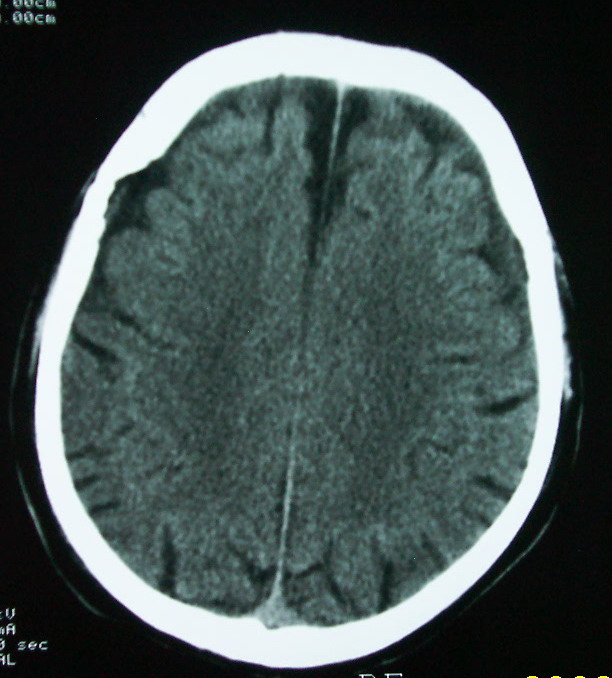

以下是引用余辉在2009-4-15 20:49:00的发言:[br]右侧病灶发生于冠状缝区,但额骨左侧鳞也有病灶,病灶区脑沟裂增宽(有脑萎缩征像,把这个征像放在颅骨病变一起考虑可能有点牵强),是否可能是板障血管畸形所致谢?抑或是嗜酸性肉芽肿或蛛网膜粒压迹那类东西?

以下是引用whzht在2009-4-15 20:57:00的发言:[br]1、额骨改变,考虑蛛网膜粒压迹;[br]2、脑萎缩。